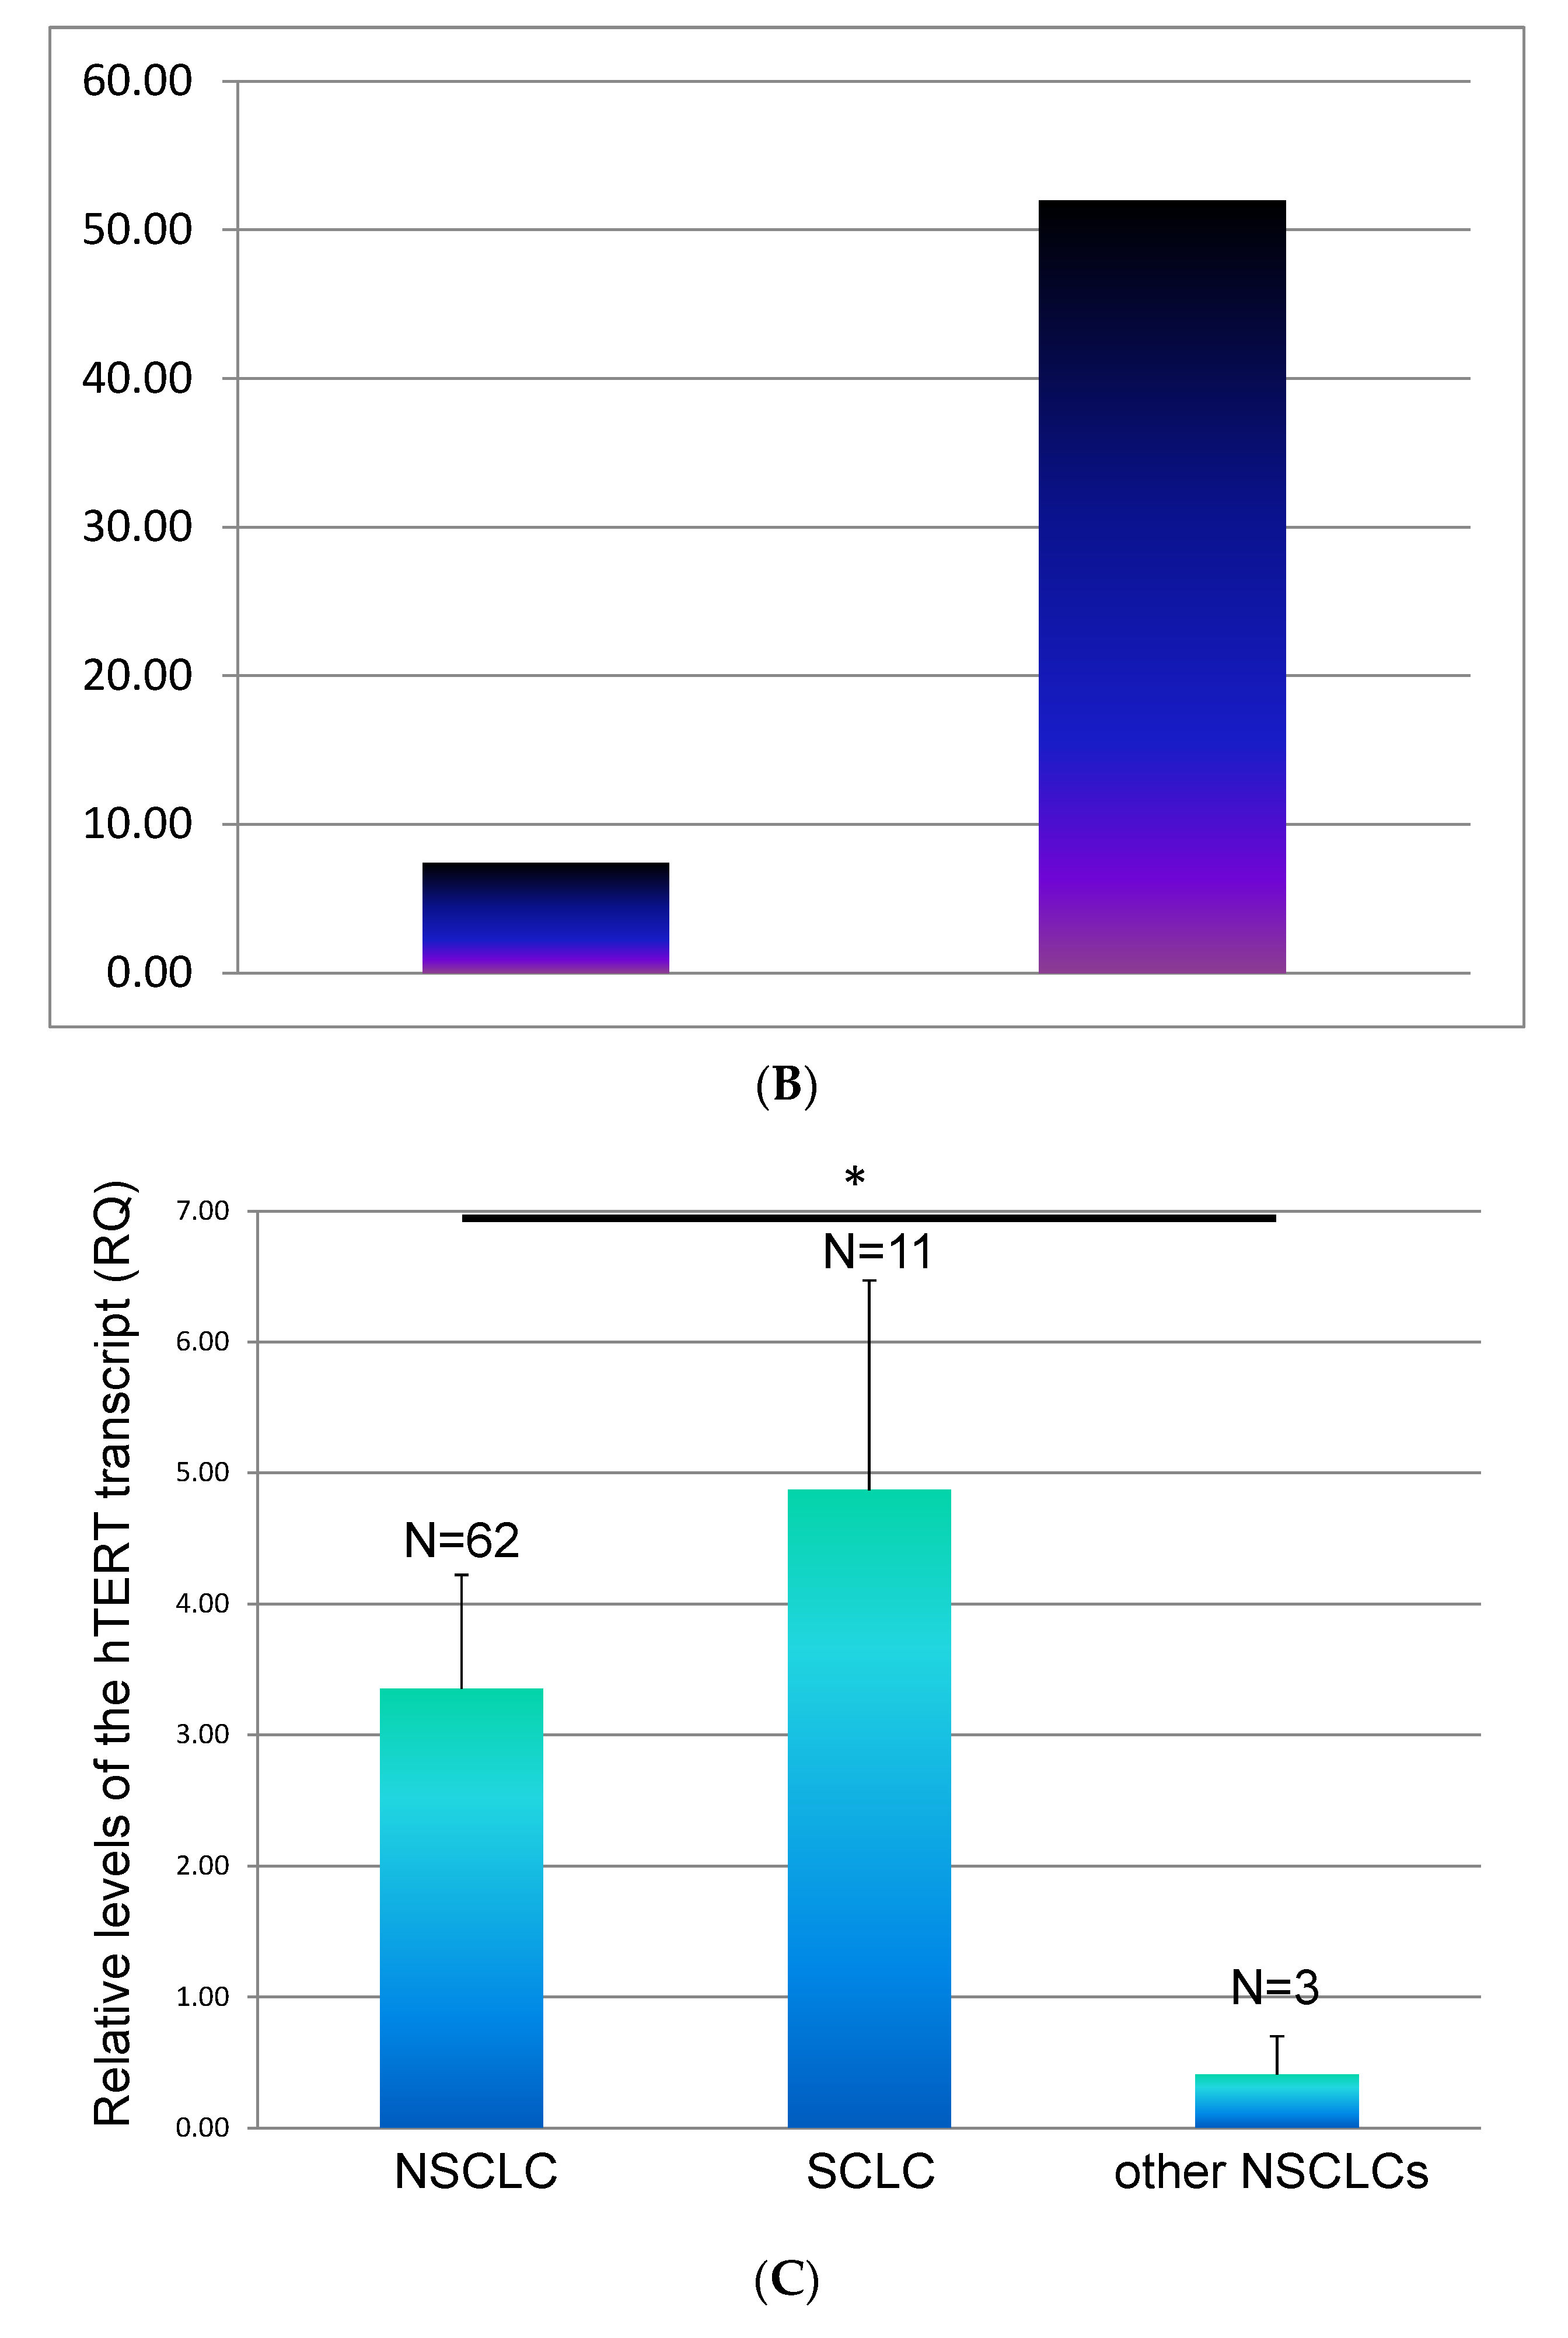

3.3. The Dynamics of hTERT at Time of Evaluation Regarding the Status of Metastasis